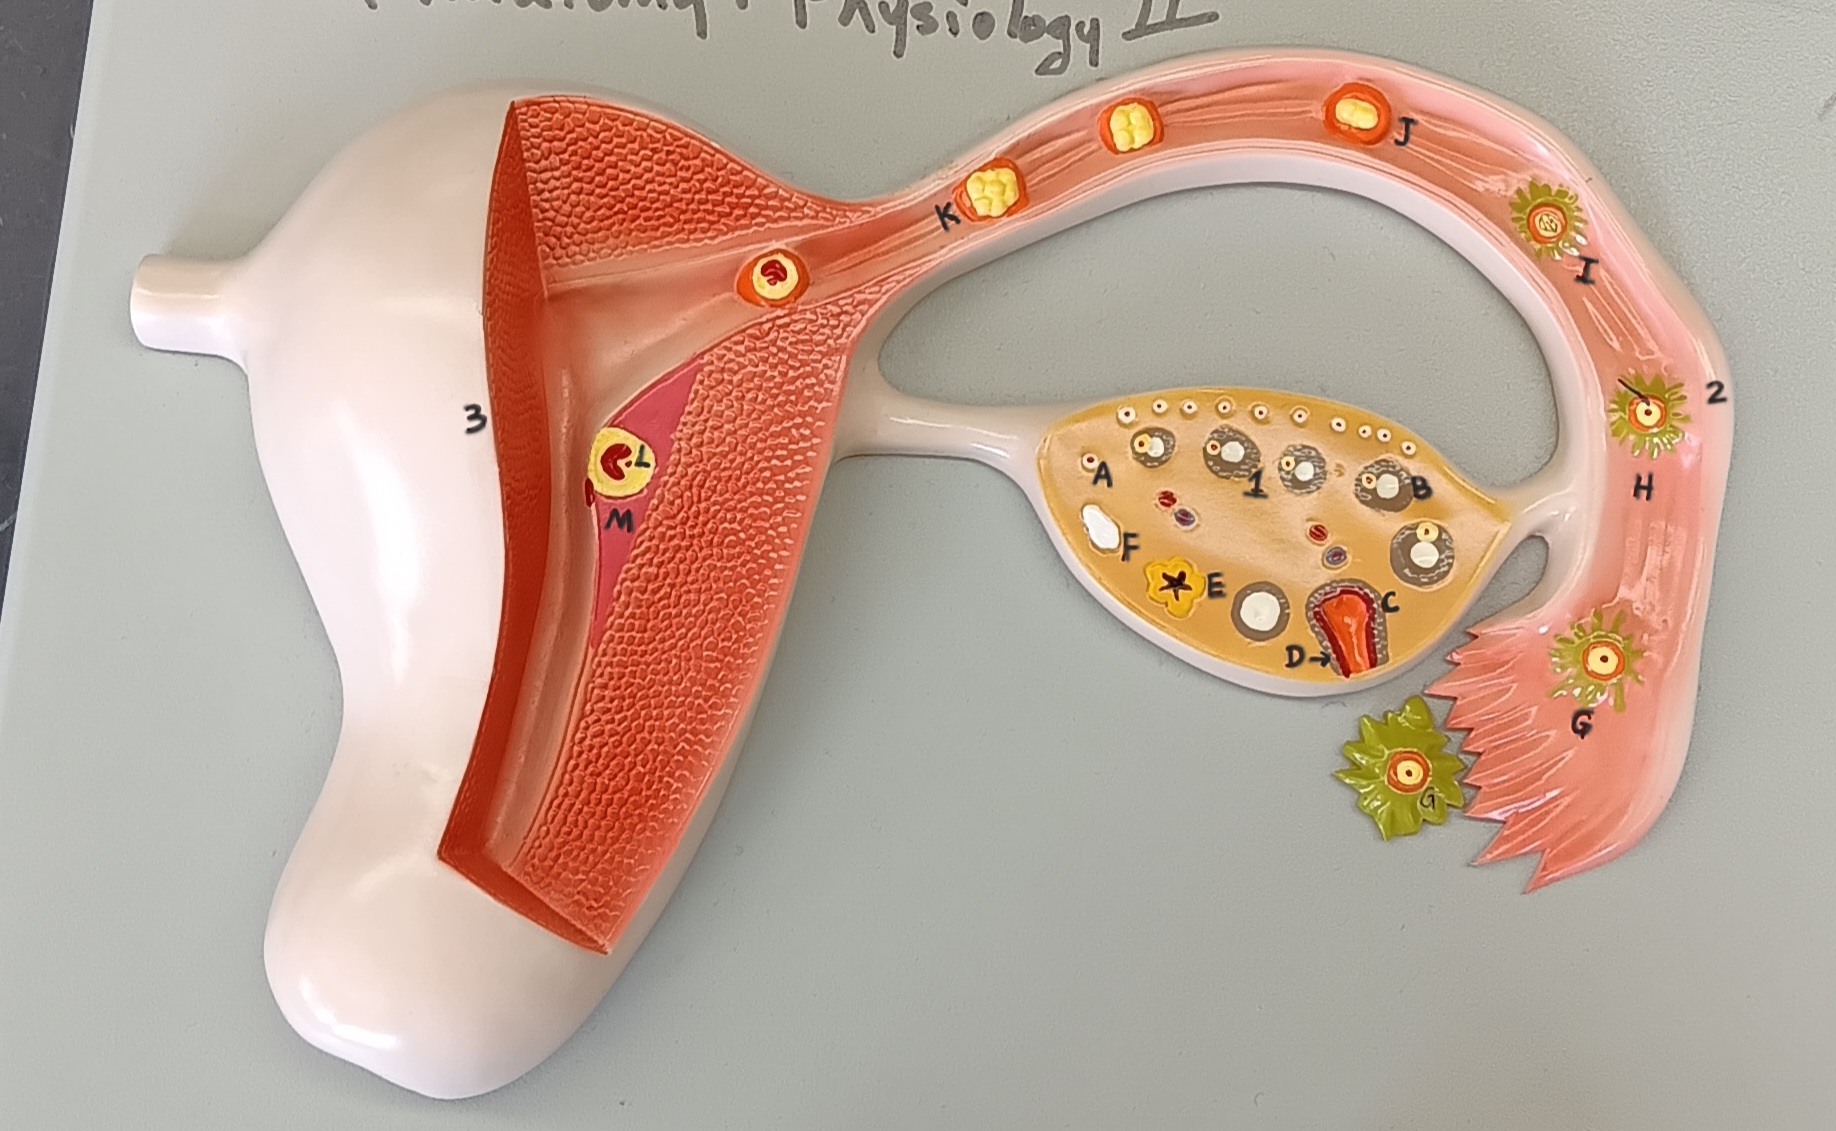

ovary

1

primordial follicle

a

secondary follicle

b

ruptured follicle

c

granulosa cells

d

corpus luteum

e

secondary oocyte

g

ovum

h

zygote

i

blastocyst

l

endometrium

m

corpus albicans

f

uterus

3

fallopian tube

2